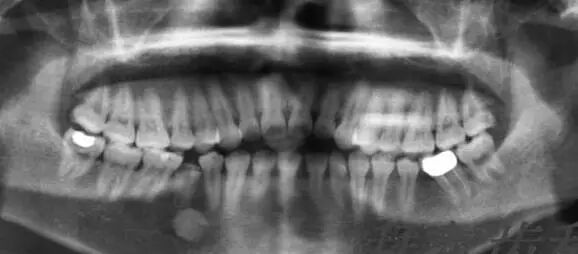

Sparse dentition, with certain teeth congenitally missing, resulting in a sparsely aligned dentition with scattered gaps, affecting aesthetics and occlusion. After orthodontic treatment, the result of the teeth is as follows: